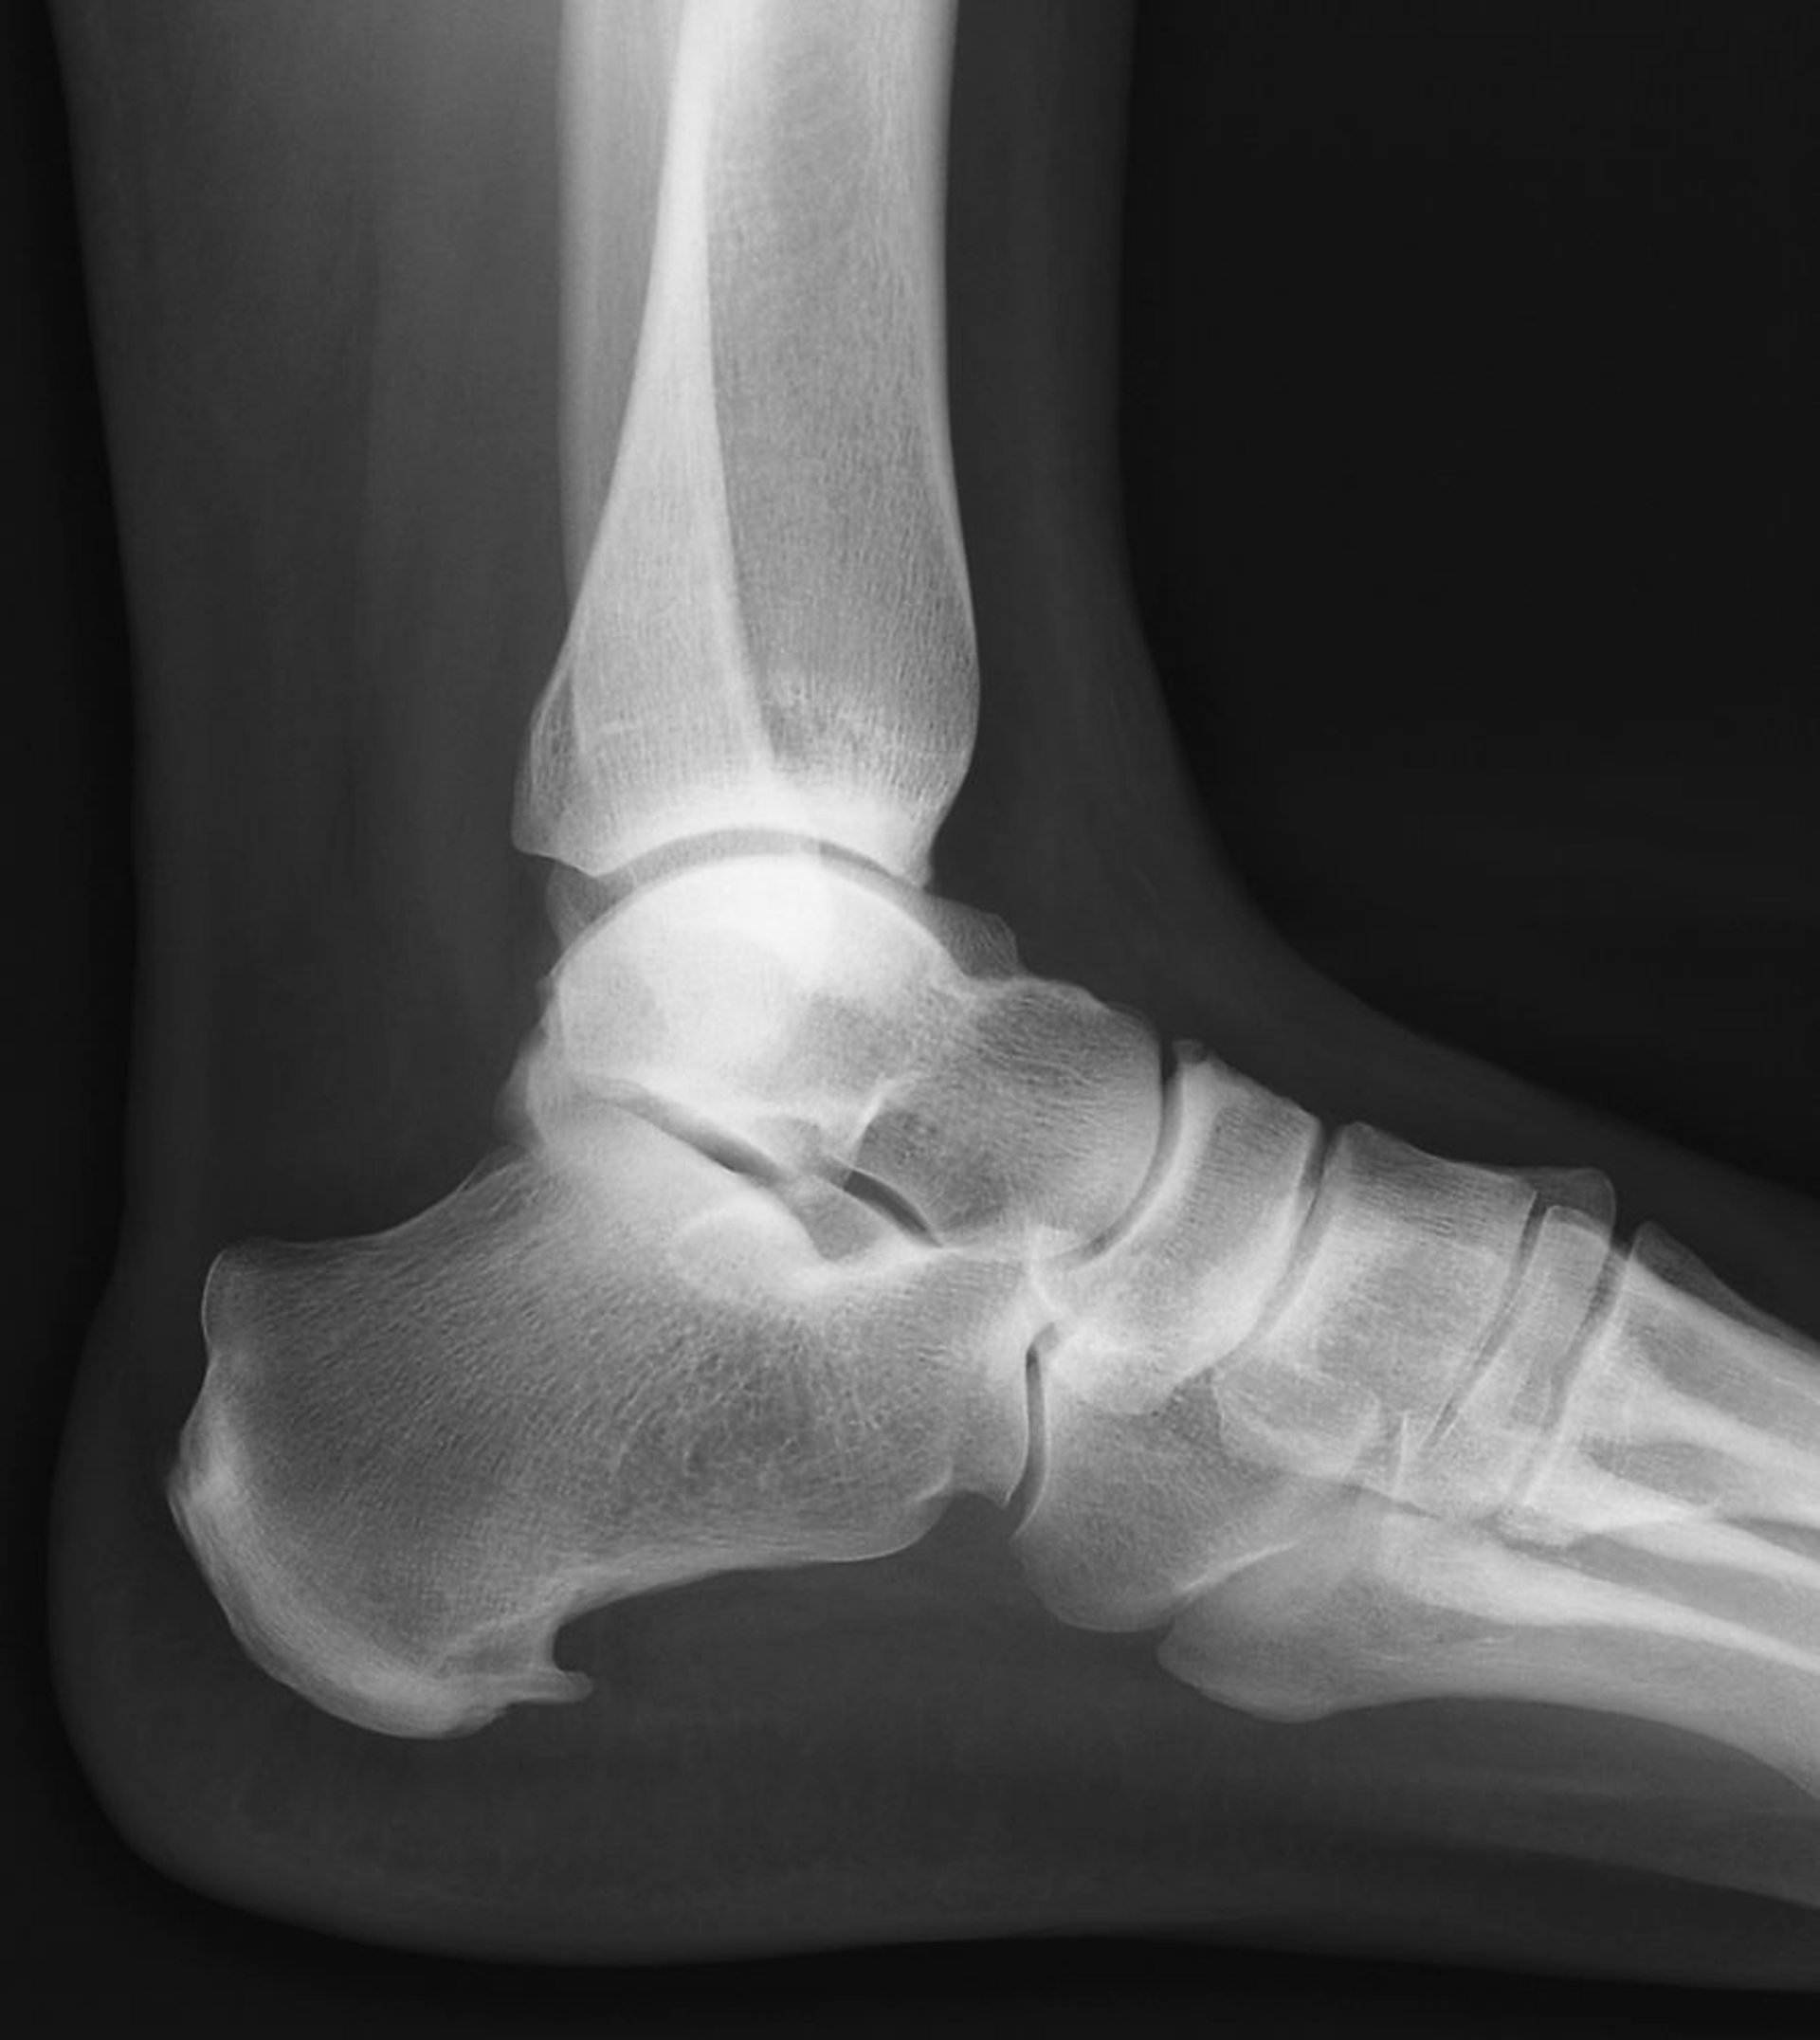

足底腱膜症は,足を背屈させた状態で踵骨を母指で強く圧迫したときに疼痛が誘発されれば確定する。筋膜の足底内側縁に沿った筋膜の疼痛があることもある。所見が曖昧な場合,X線上での踵骨棘の証明が診断を裏付けることがあるが,踵骨棘が存在しなくとも診断は除外されず,目に見える骨棘は一般的には足底腱膜症の症状の原因ではない。さらに,まれに踵骨棘がX線上で辺縁不明瞭に見え,綿状の骨新生を示すが,これは脊椎関節症(例,強直性脊椎炎,反応性関節炎)を示唆する。急性の筋膜の断裂を疑う場合,MRIを行う。